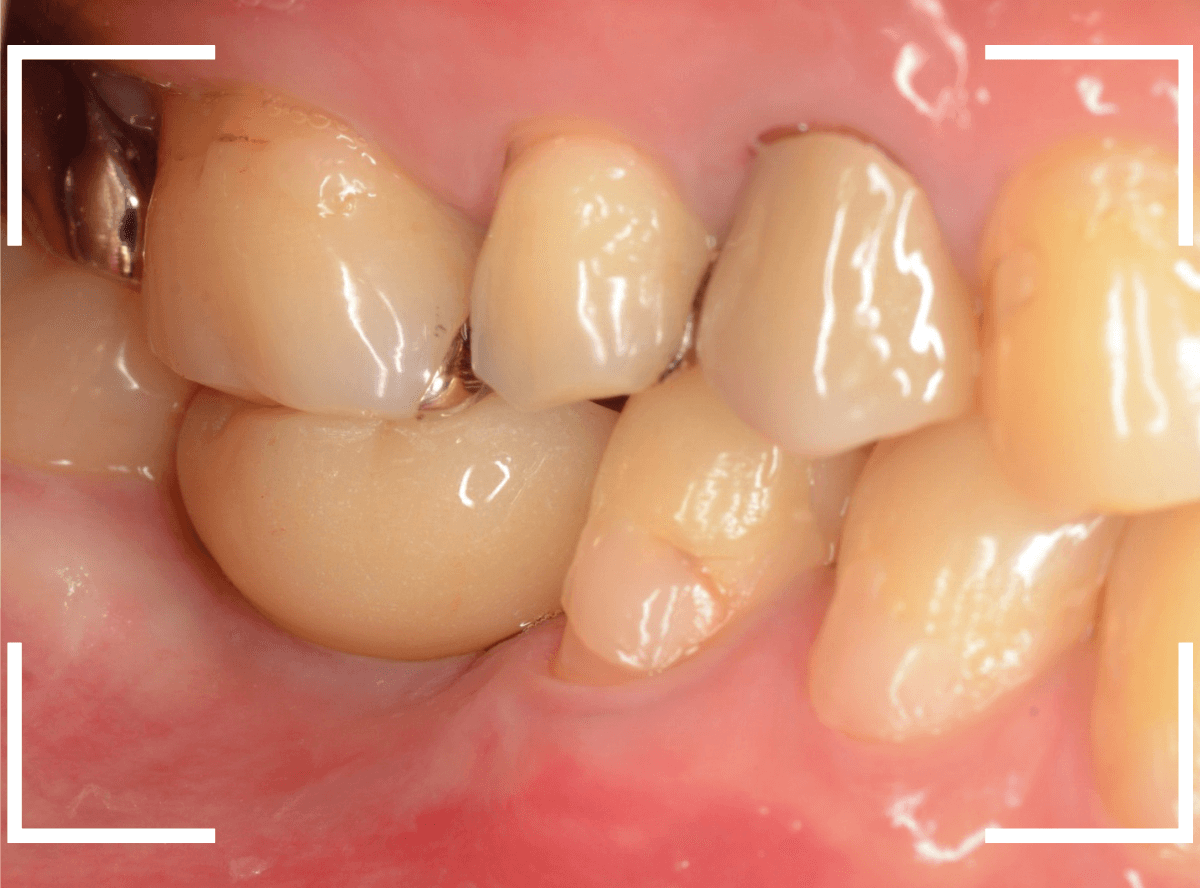

インプラントset後の状況です。

審美的にも、満足いただける仕上がりになりましたが、現在の状況を維持するために治療後の定期メンテナンスが不可欠になります(インプラントに限りませんが)。